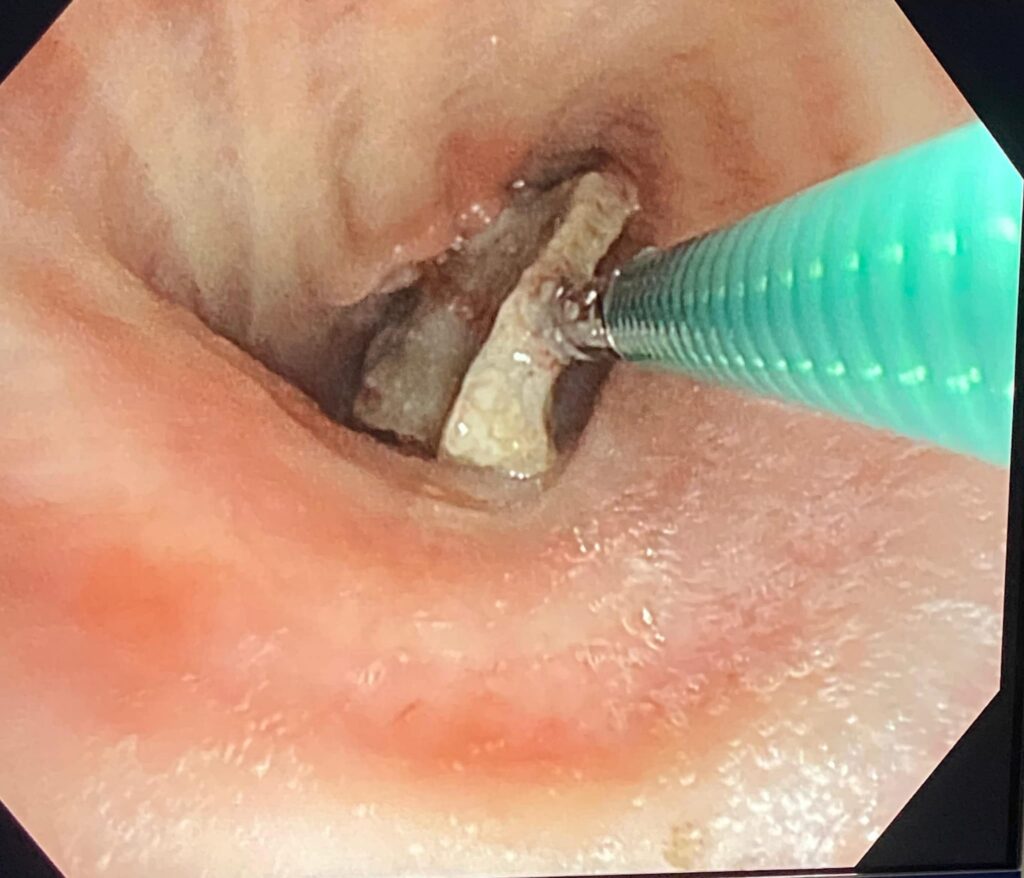

Echipa medicală a Laboratorului de Explorări Funcționale și Endoscopie Bronșică, din cadrul Spitalului de Pneumoftiziologie Sibiu, a reușit să extragă din plămânul unui pacient un os de dimensiuni mari (11 mm x 10 mm). Este vorba despre un sibian în vârstă de 63 de ani, intervenția medicală fiind efectuată de către domnul doctor Ioan Drăghilă, medic pneumolog, cu ajutorul fiber bronhoscopului, aparat aflat în dotarea laboratorului.

„Corpii endobronșici străini la adulți sunt o raritate. De obicei, pacientul uită momentul aspirării corpului străin și pot genera o simptomatologie respiratorie trenantă. La pacientul nostru, retrospectiv, am aflat că momentul inhalării corpului străin a fost în luna februarie, deci în urmă cu circa 4 luni, timp în care pacientul a continuat să prezinte tuse și infecții respiratorii repetate. La examenul CT , pentru că nu exista diagnostic, s-a relevat prezența unui corp străin cu aspect de os, în plămân, acest corp străin fiind extras cu succes de către echipa de bronhologie a Spitalului de Pneumoftiziologie Sibiu, după o pregătire prealabilă corespunzătoare a pacientului. Sperăm că evoluția post intervenție va fi favorabilă și în acest fel episoadele pneumonice repetate pe care pacientul le-a prezentat, să nu se mai repete” – a declarat dr. Ioan Drăghilă, medic pneumolog, șeful Secției Pneumologie II din cadrul Spitalului de Pneumoftiziologie Sibiu.

Imaginile extracției: